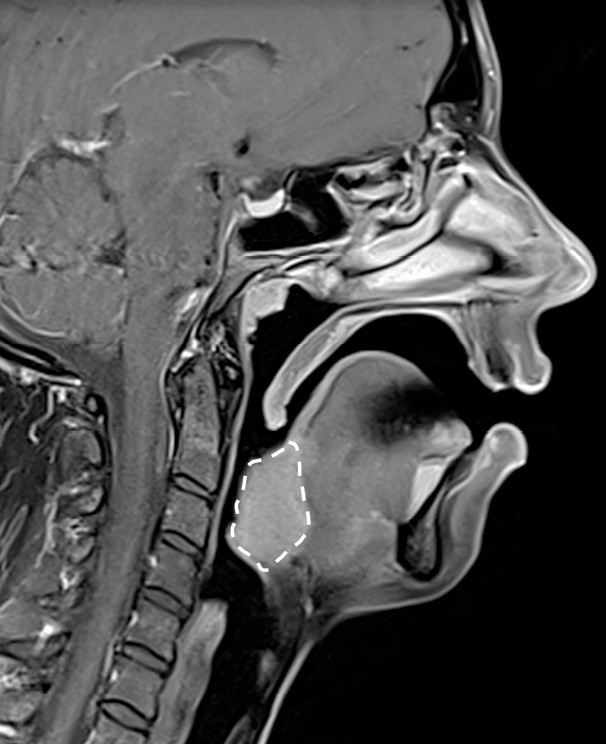

Le collapsus pharyngé à l’origine du SAOS peut résulter de mécanismes variés, souvent associés. L’hypertrophie des tissus mous (amygdales, base de langue, parois pharyngées) en est l’une des causes possibles, fréquemment liée au surpoids observé dans cette pathologie.

L’étroitesse squelettique peut également être impliquée (rétromandibulie, hyperdivergence, endognathie) [1] (fig. 1-4).

Il est nécessaire, pour la recherche d’un site obstructif…